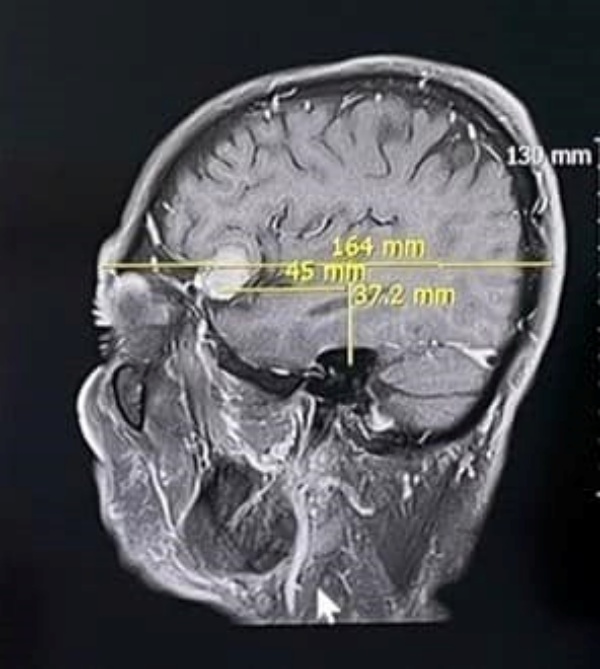

แพทย์ได้ตรวจอาการเบื้องต้น สงสัยอาจมีความผิดปกติทางสมอง จึงส่งตรวจคลื่นแม่เหล็กไฟฟ้าสมอง พบเป็นเนื้องอกในสมอง ขนาดประมาณ 2 เซนติเมตร จึงส่งปรึกษาแพทย์ผู้เชี่ยวชาญด้านศัลยศาสตร์ระบบประสาท ที่โรงพยาบาลประจวบคีรีขันธ์